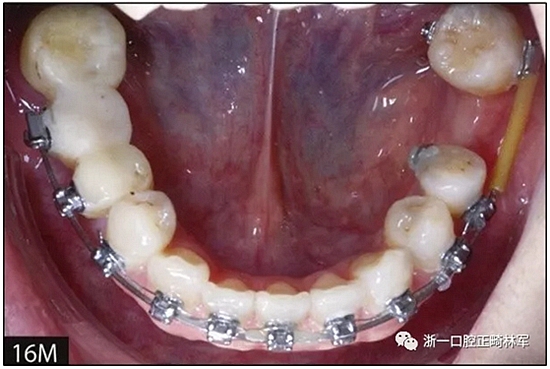

完全固定的Damon Q設(shè)備(加利福尼亞州Glendora的Ormco)與制造商指定的弓絲和附件一起使用。下頜弓,一開始放入0.014英寸的鎳鈦弓絲,5個月后放入0.014×0.025英寸的鎳鈦弓絲。舌側(cè)扣和鏈圈放置在下頜尖牙和第二前磨牙上以控制扭轉(zhuǎn)。在治療的第7個月,將下頜弓絲換成0.017× 0.025英寸的β鈦絲。另一個舌側(cè)扣和鏈圈放置在下頜左側(cè)第三磨牙上以提供近中牽引力(圖9)。在16個月的治療結(jié)束時,所有的扭轉(zhuǎn)都得到了矯正,缺牙間隙縮小到8 mm(圖8),但由于頰側(cè)骨板的嚴重吸收,牙槽嵴的寬度仍然很窄(約3 mm)(圖9)。通過正畸移動下頜左側(cè)第二前磨牙,在前磨牙之間產(chǎn)生一個種植部位。在第一和第二前磨牙之間的弓絲上放置一個推簧,并將舌側(cè)扣和鏈圈放置在第一前磨牙和第三磨牙之間(圖9),在頰側(cè)和舌側(cè)施加力。施力均為輕力,每個表面上約2盎司(28.3 cN)以控制牙根側(cè)面的吸收。

圖8